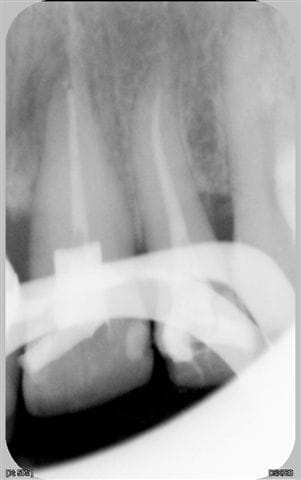

voici un cas traité en dentisterie globale à l'aide du laser en paro et du cerec en occluso, le cas à été terminé en 2010, cette semaine examen microbiologique de routine avec maintenance paro, il n'y a plus de flore pathologique dans la bouche de cette patiente

Emma

Reste plus qu'à faire des greffes de gencives secteur 4.

Tu as une radio zone 11-21, perte de papille importante.

salut ceramik, toujours aussi contente de te lire, tes désirs sont des ordres, radios faites en 2010, les photos dates de juin 2010, les papilles entre 11 et 21 sont entrain de se reconstruire petit à petit, au prochain contrôle de maintenance, je ferai des radios et des photos pour montrer l'évolution engendrée par la biostimulation laser diode.

Sur les radio, l'os interdentaire est môches, la règle de Tarnow (5mm) pt de conct et crête osseuse pour les papille n'y est pas... La modification du contact sur les couronnes comme suggéré serait la chose à faire...